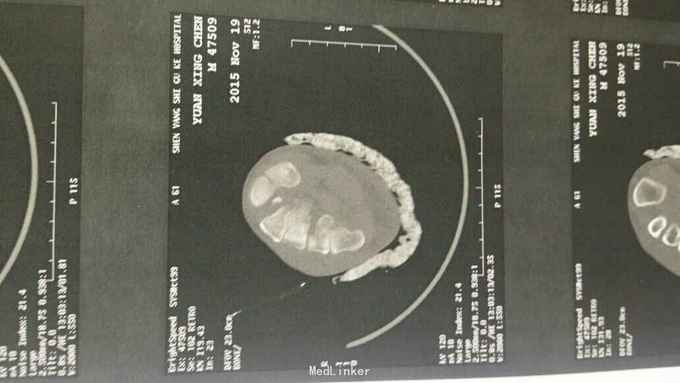

主诉:右足外伤后肿痛,活动受限11天。 现病史:患者于2015年11月10日摔伤右足,当即肿痛,活动受限,急去当地医院拍片及入院行石膏固定保守治疗,效果不佳,为求进一步治疗来诊我院,经门诊阅片及查体后以“右足多发骨折,脱位,韧带损伤”为诊断收入院。

查体:右足略肿胀,畸形明显,足背压痛广泛阳性,可触及骨擦音及骨察感,活动受限,末梢各趾活动自如,足背动脉清。 辅助检查:大致正常。

诊断:右足多发骨折伴跖跗关节脱位,韧带损伤 治疗:患者入院后,完善检查,于2015年11月25日行手术治疗,现切口愈合良好。